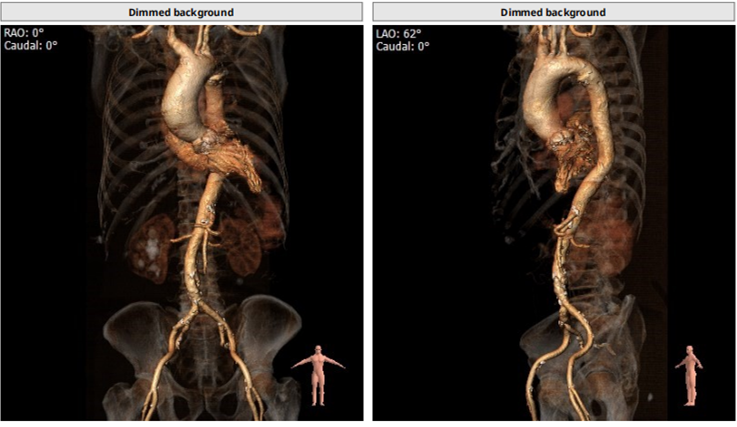

根部解剖

患者为TYPE0二叶瓣,重度钙化,术前可见瓣周突出物,怀疑囊肿,瓣环23.8,LVOT25.5,鱼嘴开口22.8,预计瓣口开口22.3,STJ33.9,窦部空间大,左右冠高度分别为19.9和21.5,预计18号球囊预扩。

入路: